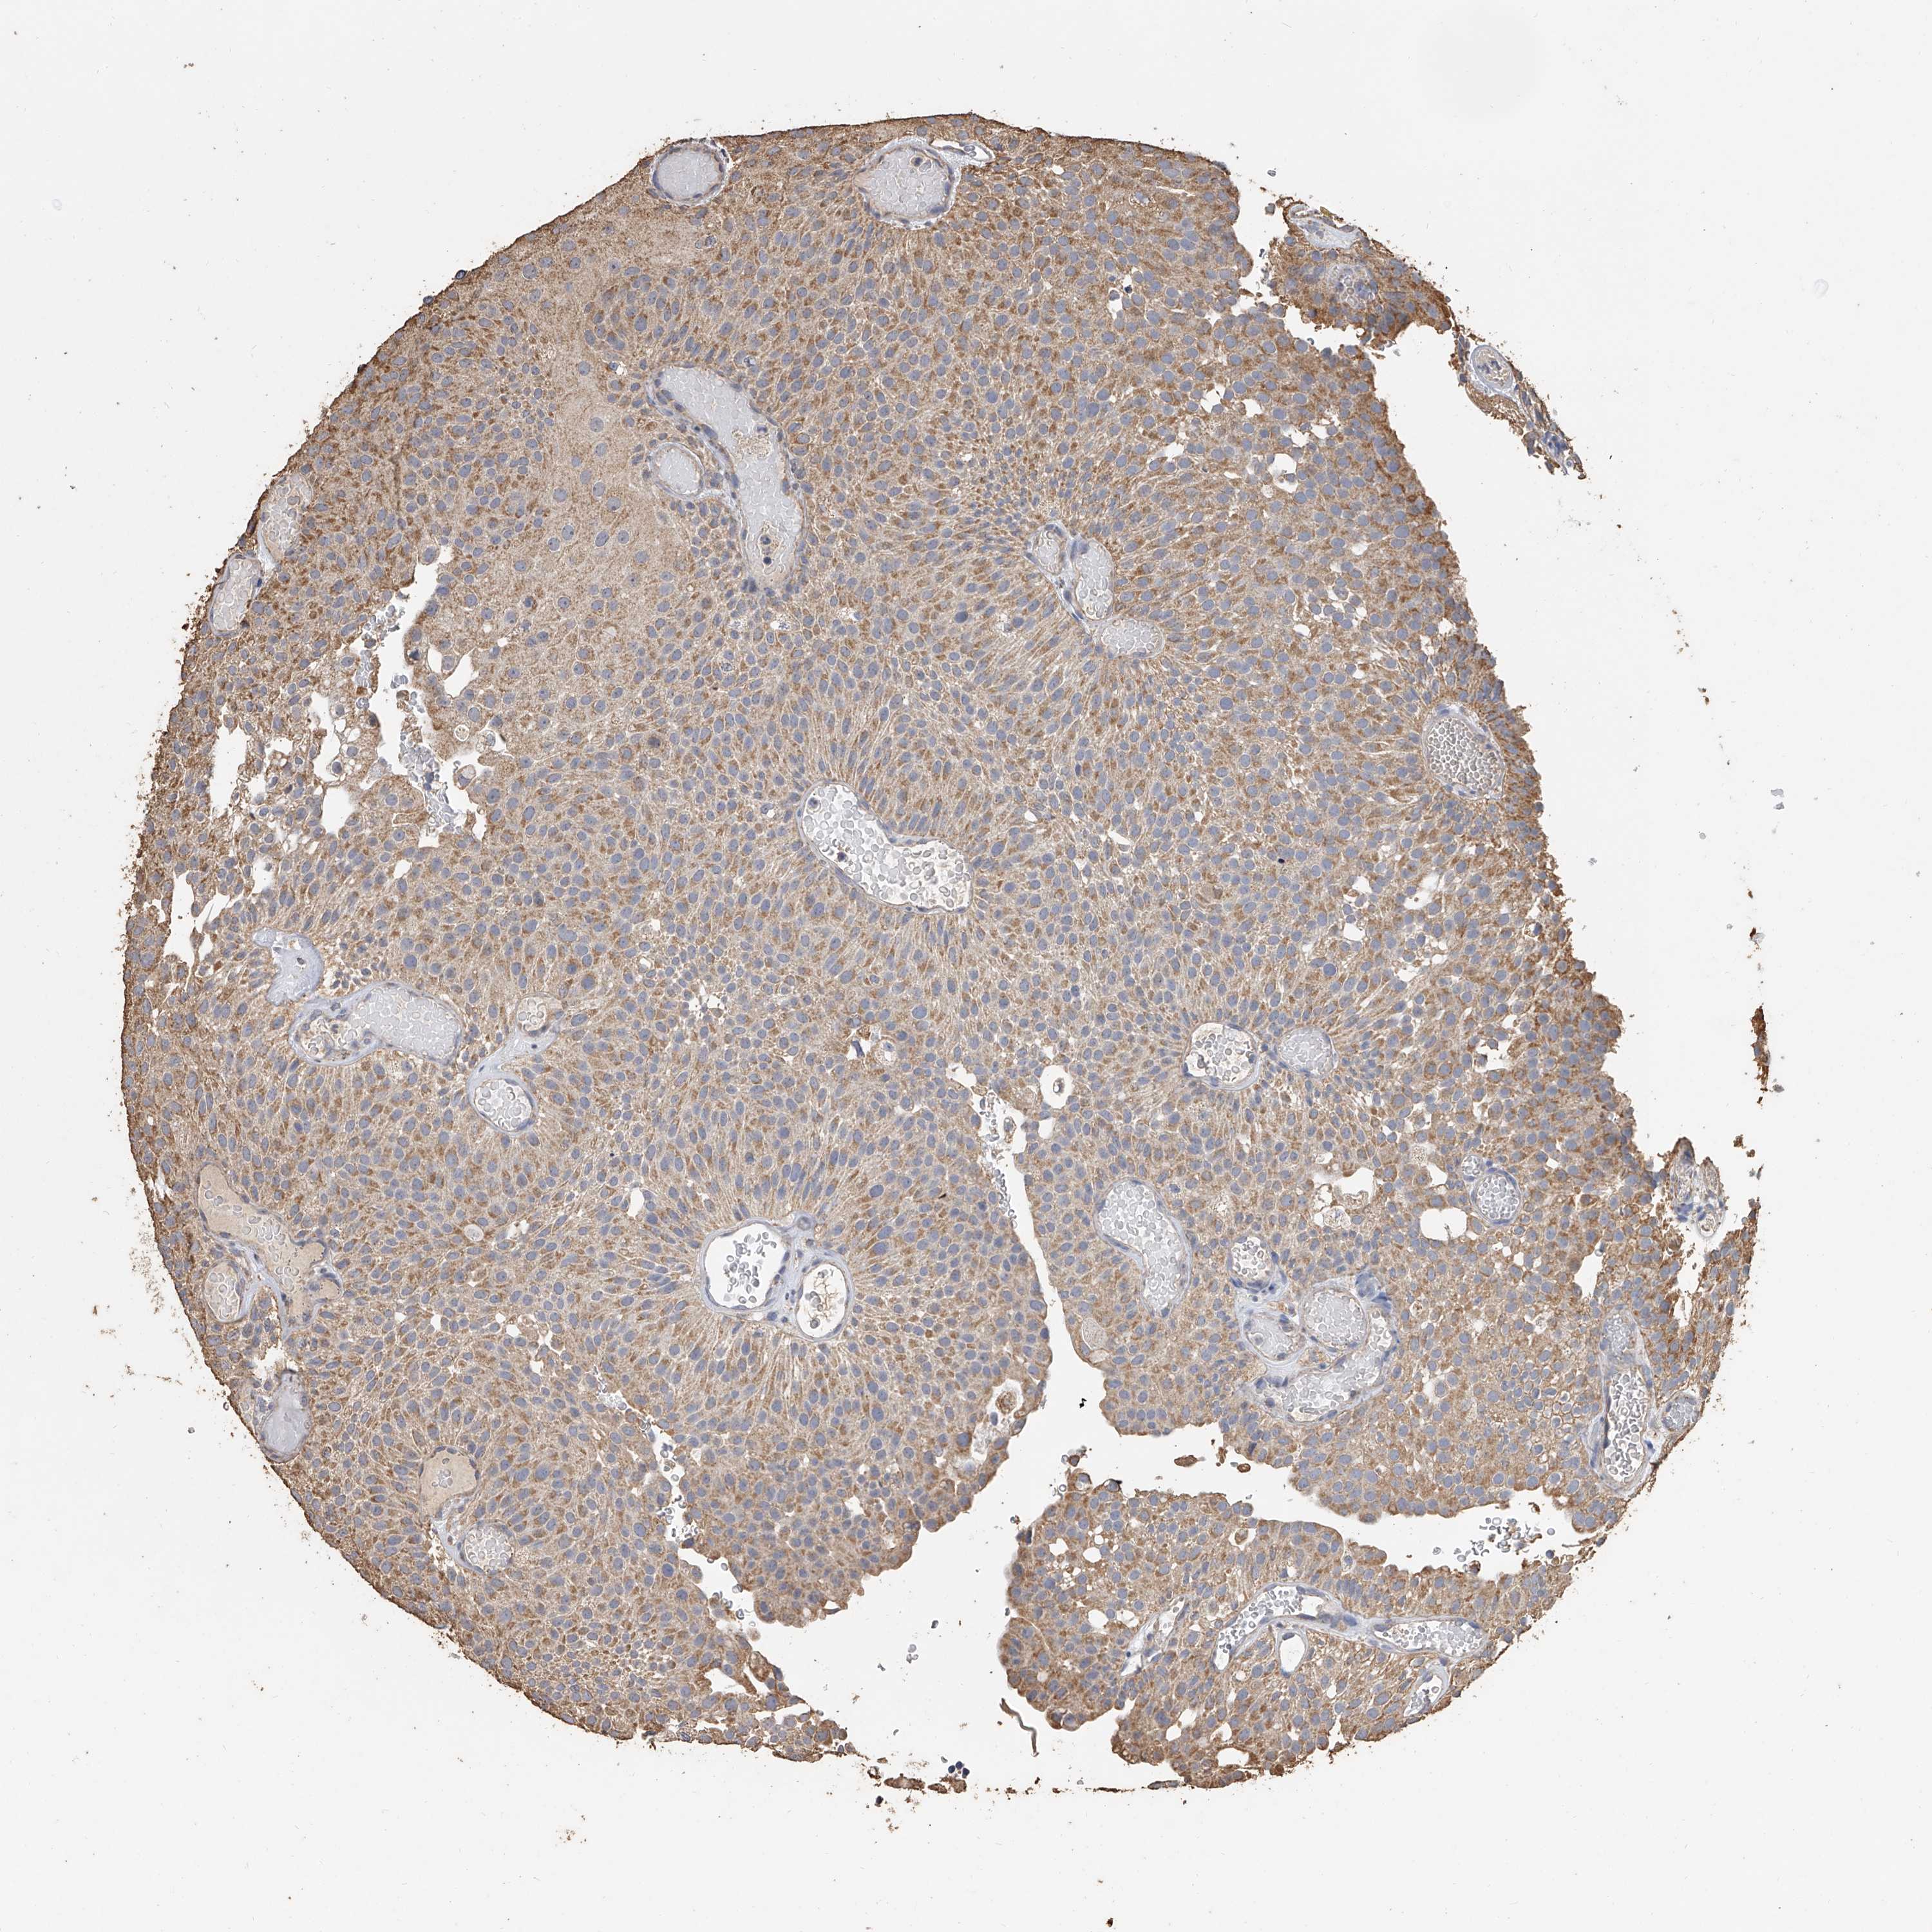

UROTHELIAL CANCER - Protein expressioni

A mouse-over function shows sample information and annotation data. Click on an image to view it in a full screen mode. Samples can be filtered based on level of antibody staining by selecting one or several of the following categories: high, medium, low and not detected. The assay and annotation is described here.

Note that samples used for immunohistochemistry by the Human Protein Atlas do not correspond to samples in the TCGA dataset.

Antibody stainingi

Antibody staining in the annotated cell types in the current human tissue is reported as not detected, low, medium, or high, based on conventional immunohistochemistry profiling in selected tissues. This score is based on the combination of the staining intensity and fraction of stained cells.

Each image is clickable and will lead to virtual microscopy that enables deeper exploration of all samples and also displays staining intensity scores, fraction scores and subcellular localization as well as patient and tissue information for each sample.

Antibody HPA030594

Antibody HPA055589

Antibody CAB033542

Staining

High

Medium

Low

Not detected

Intensity

Strong

Moderate

Weak

Negative

Quantity

>75%

75%-25%

<25%

None

Location

Nuclear

Cytoplasmic/membranous

Cytoplasmic/membranous,nuclear

Urothelial carcinoma, Low grade

Urothelial carcinoma, High grade

Urothelial carcinoma, NOS